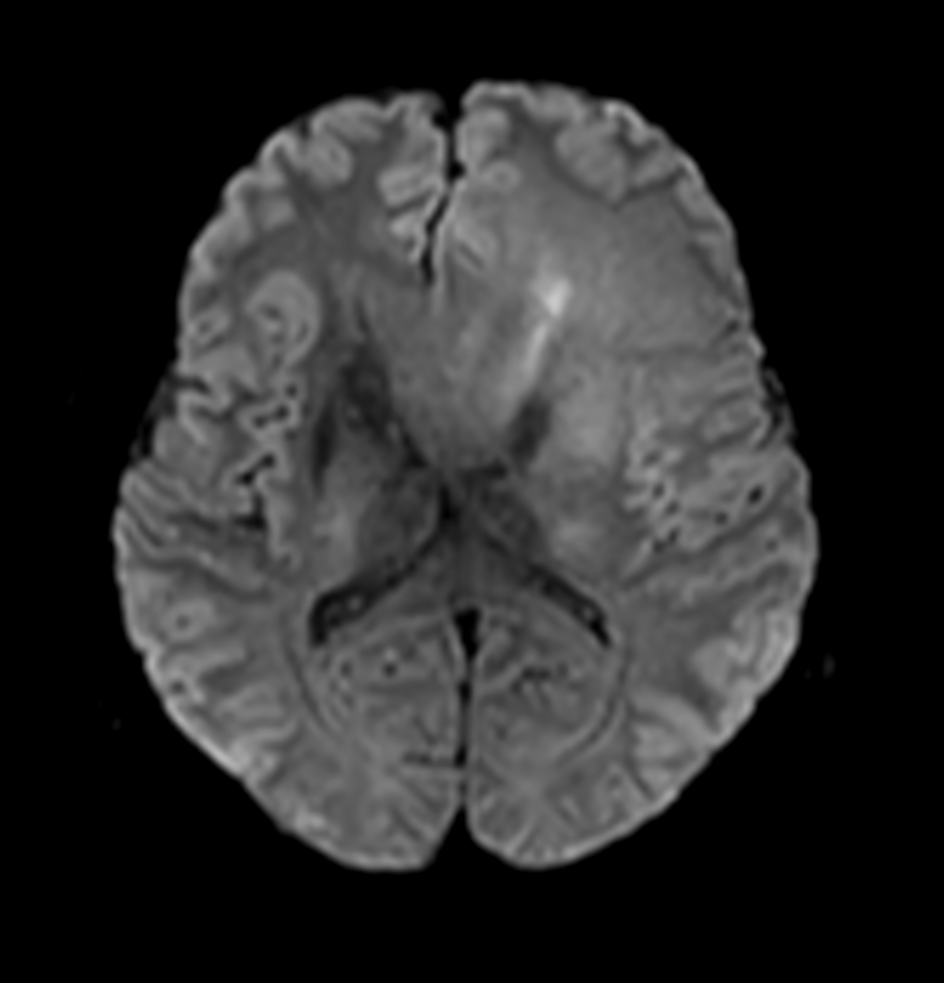

DWI (b1000)

DWI (ADC)

DWI (eADC)